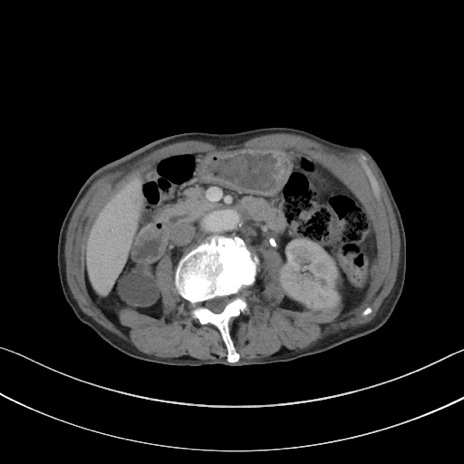

症例3(横断像)

【症例】 70歳代男性

【主訴】右鼠径部腫瘤、疼痛

【現病歴】本日朝より上記主訴あり、受診。

【既往歴】膀胱癌にて膀胱全摘、両側尿管皮膚瘻

【データ】WBC 5600、CRP 0.56